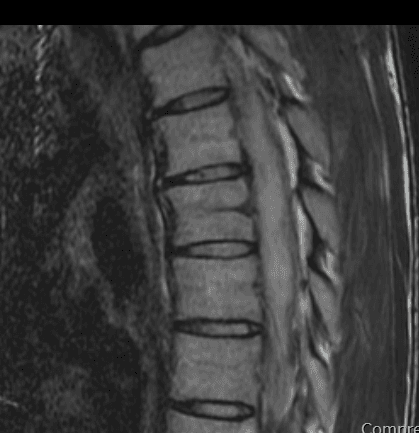

안녕하세요. 남희성 의사입니다.

이런 경우에 골절이 아닌지 오해하시는 경우가 많은데 골절이 아닙니다.

골절의 경우에는 T1 영상에서 조영이 떨어지고 fat suppression T2 영상에서 조영이 증가하는 소견을 확인해야합니다.

골절이 아니면 왜 저렇게 보이는지 까지는 제가 잘 모르지만 저 소견을 이상소견으로 보이는 않습니다.